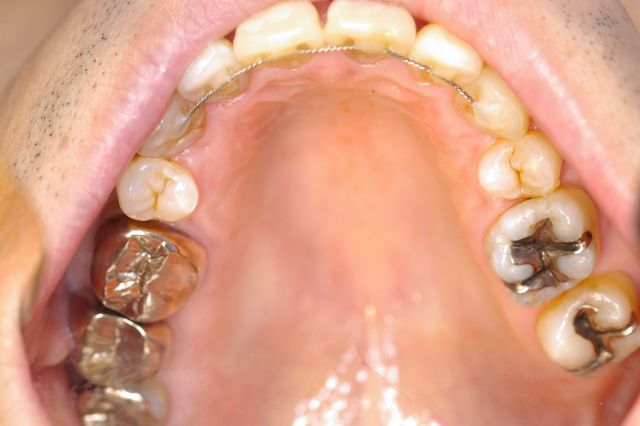

| @上顎前突(矯正用インプラント使用症例) | |||||||||||||||||||||||||||||||||||

かなり重度の上顎前突症例です。 バードフェイス(鳥貌)と言われる横顔で、以前(2000年頃まで)は矯正不可能と言われていた症例ですが 矯正用インプラント(矯正用ビス)を入れることにより、短期間で改善できた例です。 尚、矯正用インプラントは、力がかかる時だけ入れるもので使用後は簡単に外せます。 矯正用インプラントは、2000年頃より日本に導入された治療法です。(詳しくは、コチラ) もちろん、矯正用インプラントを使用しなくても治る症例も沢山あります。 |

上顎の歯槽骨までも後ろに後退させて側貌も改善されています。(顔は伏せています。) 歯並びだけではなく、顔の見た目も改善することが矯正の目標と考えています。 また、歯列もV字型の咬み合わせからU字型になって咬み合わせも良くなり、口元の審美性も改善されています。 |

| また、矯正期間をかなり短縮できる利点があります。 矯正期間1年6カ月 欠点は、インプラントを埋めることですが、小さなビス(長さ8mm直径1.8mm程度)なので簡単に出来ます。 また、インプラントを除去後は、粘膜、骨は完全に元に戻りますので心配いりません。 |